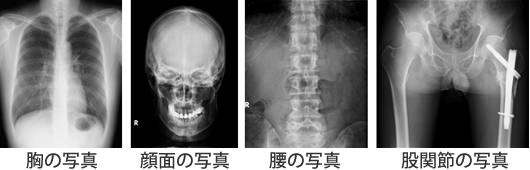

胸や腹、骨などの撮影を総称して「一般撮影」といいます。いわゆるレントゲン撮影です。X線を用いて撮影することで痛みを伴わずに、体の内部を見ることができます。